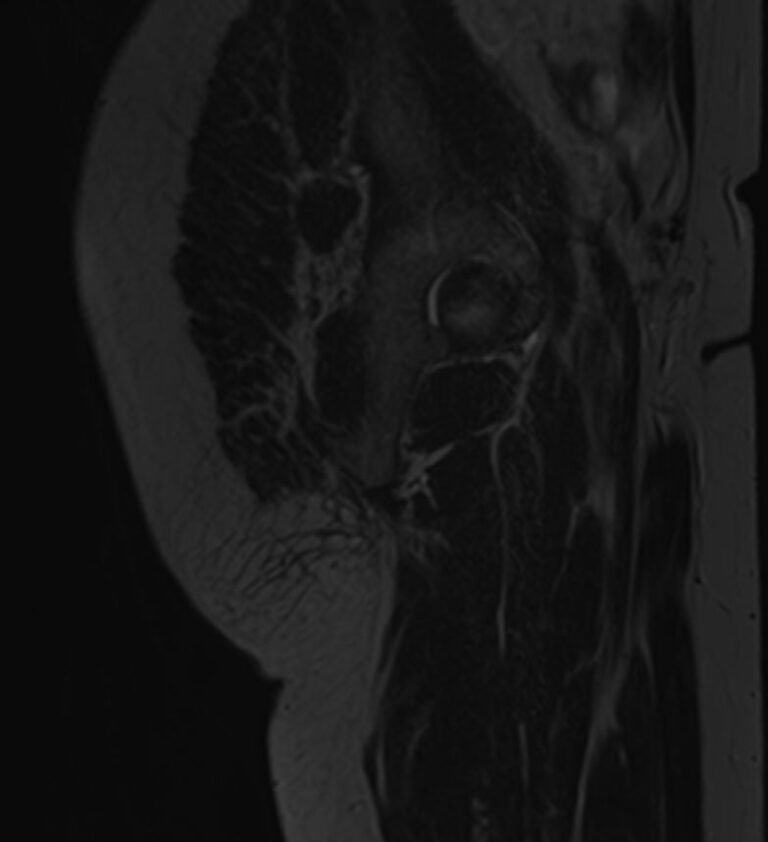

Чаще всего ягодичная область подвержена развитию воспалительных заболеваний, травматических повреждений и опухолевых процессов. Наиболее эффективным способом диагностики патологии мягких тканей ягодичной области является магнитно-резонансная томография. При применении данного метода не используется вредное ионизирующее излучение, как при обычном рентгене или КТ, при этом МРТ дает наибольшую информацию о состоянии мягкотканных структур, выявляя патологические очаги размером от 1 мм.

МРТ данной анатомической области выполняется в большинстве случаев в стандартном режиме без применения контрастного усиления. Однако при подозрении на развитие опухоли необходимо введение контрастного препарата. Для этого используется контрастное вещество, созданное на основе гадолиния (металл, обладающий особыми свойствами в зоне действия магнитного поля). Контраст избирательно накапливается в очагах поражения и обусловливает их яркое свечение под влиянием магнитного поля томографа. Это позволяет, в частности, выявлять опухоли на ранних стадиях развития и дает исчерпывающую информацию о структуре опухолевого образования, его границах, степени кровоснабжения и распространения на близлежащие органы и ткани.

При проведении МРТ можно выявить следующие заболевания ягодичной области:

- Доброкачественные и злокачественные опухоли, которые располагаются в мягких тканях ягодичной области.